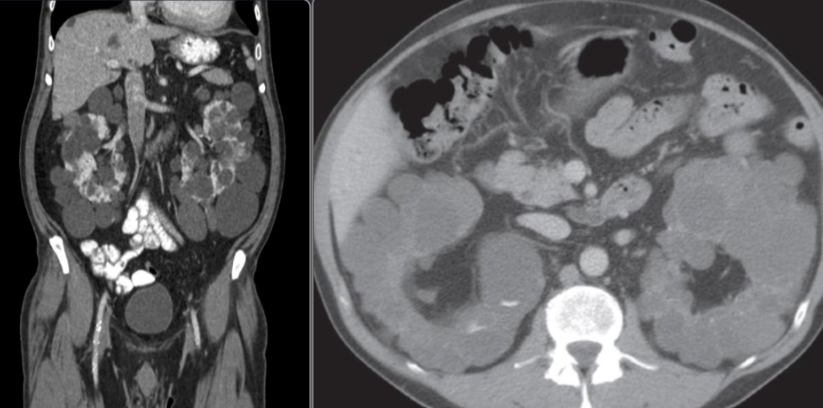

CT Brain IN EMERGENCY

Epidural hematoma

- Convex inner margin (lens-shaped)

- High density area

CT brain - Acute subdural hemorrhage

- crescent shape

CT brain - Chronic subdural hemorrhage

- Concave

CT brain - Acute on chronic subdural hematoma

- Inner margins are concave